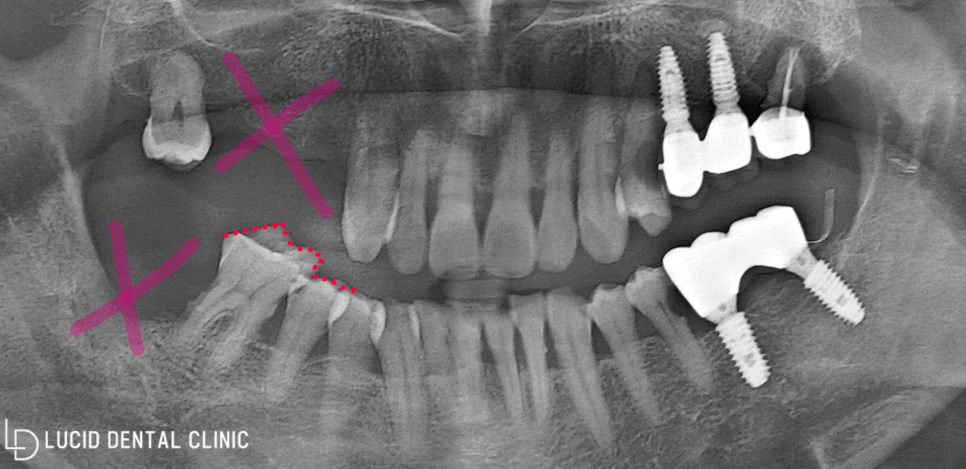

- 정밀 구강 검진 결과

보다 자세히 관찰할 수 있도록

파노라마 엑스레이를 촬영했습니다.

사진과 같이 수복 받았던 치료와

크라운까지 관찰이 가능합니다.

제가 빨갛게 표시해 드린 곳을 보면

상태가 좋지 않다는 것을 알 수 있는데요

이미 치아를 발치하여 공간이 비어있고,

제대로 처치하지 않아 정출이 나타났습니다.

이런 상태로라면 제대로 된 식사가 이뤄지지 않아

잘못하다간 영양실조로 이어질 수 있는 문제입니다.

즉, 구강 질환뿐만 아니라 전신 질환까지

이어질 수 있다는 적신호라는 것이죠.